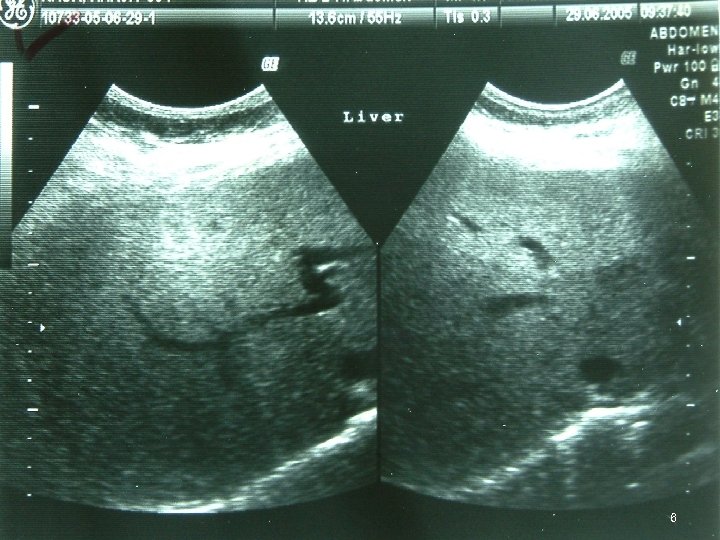

Investigations • • • Chest X Ray USG CECT EUS Ba Swallow 3

4

5

6

7

8